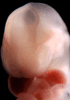

Carnegie Stage 14 (32 post-ovulatory days)

Most embryos at stage 14 are approximately 32 postovulatory days old and measure 5-7 mm in length. Distinguishing criteria for this stage include an open lens pit with invagination of the lens disc and elongated and tapering upper limb buds. The otic vesicle with a well-defined endolymphatic appendage is also a hallmark of this stage.